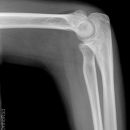

nicht dislozierte Radiusköpfchenfraktur